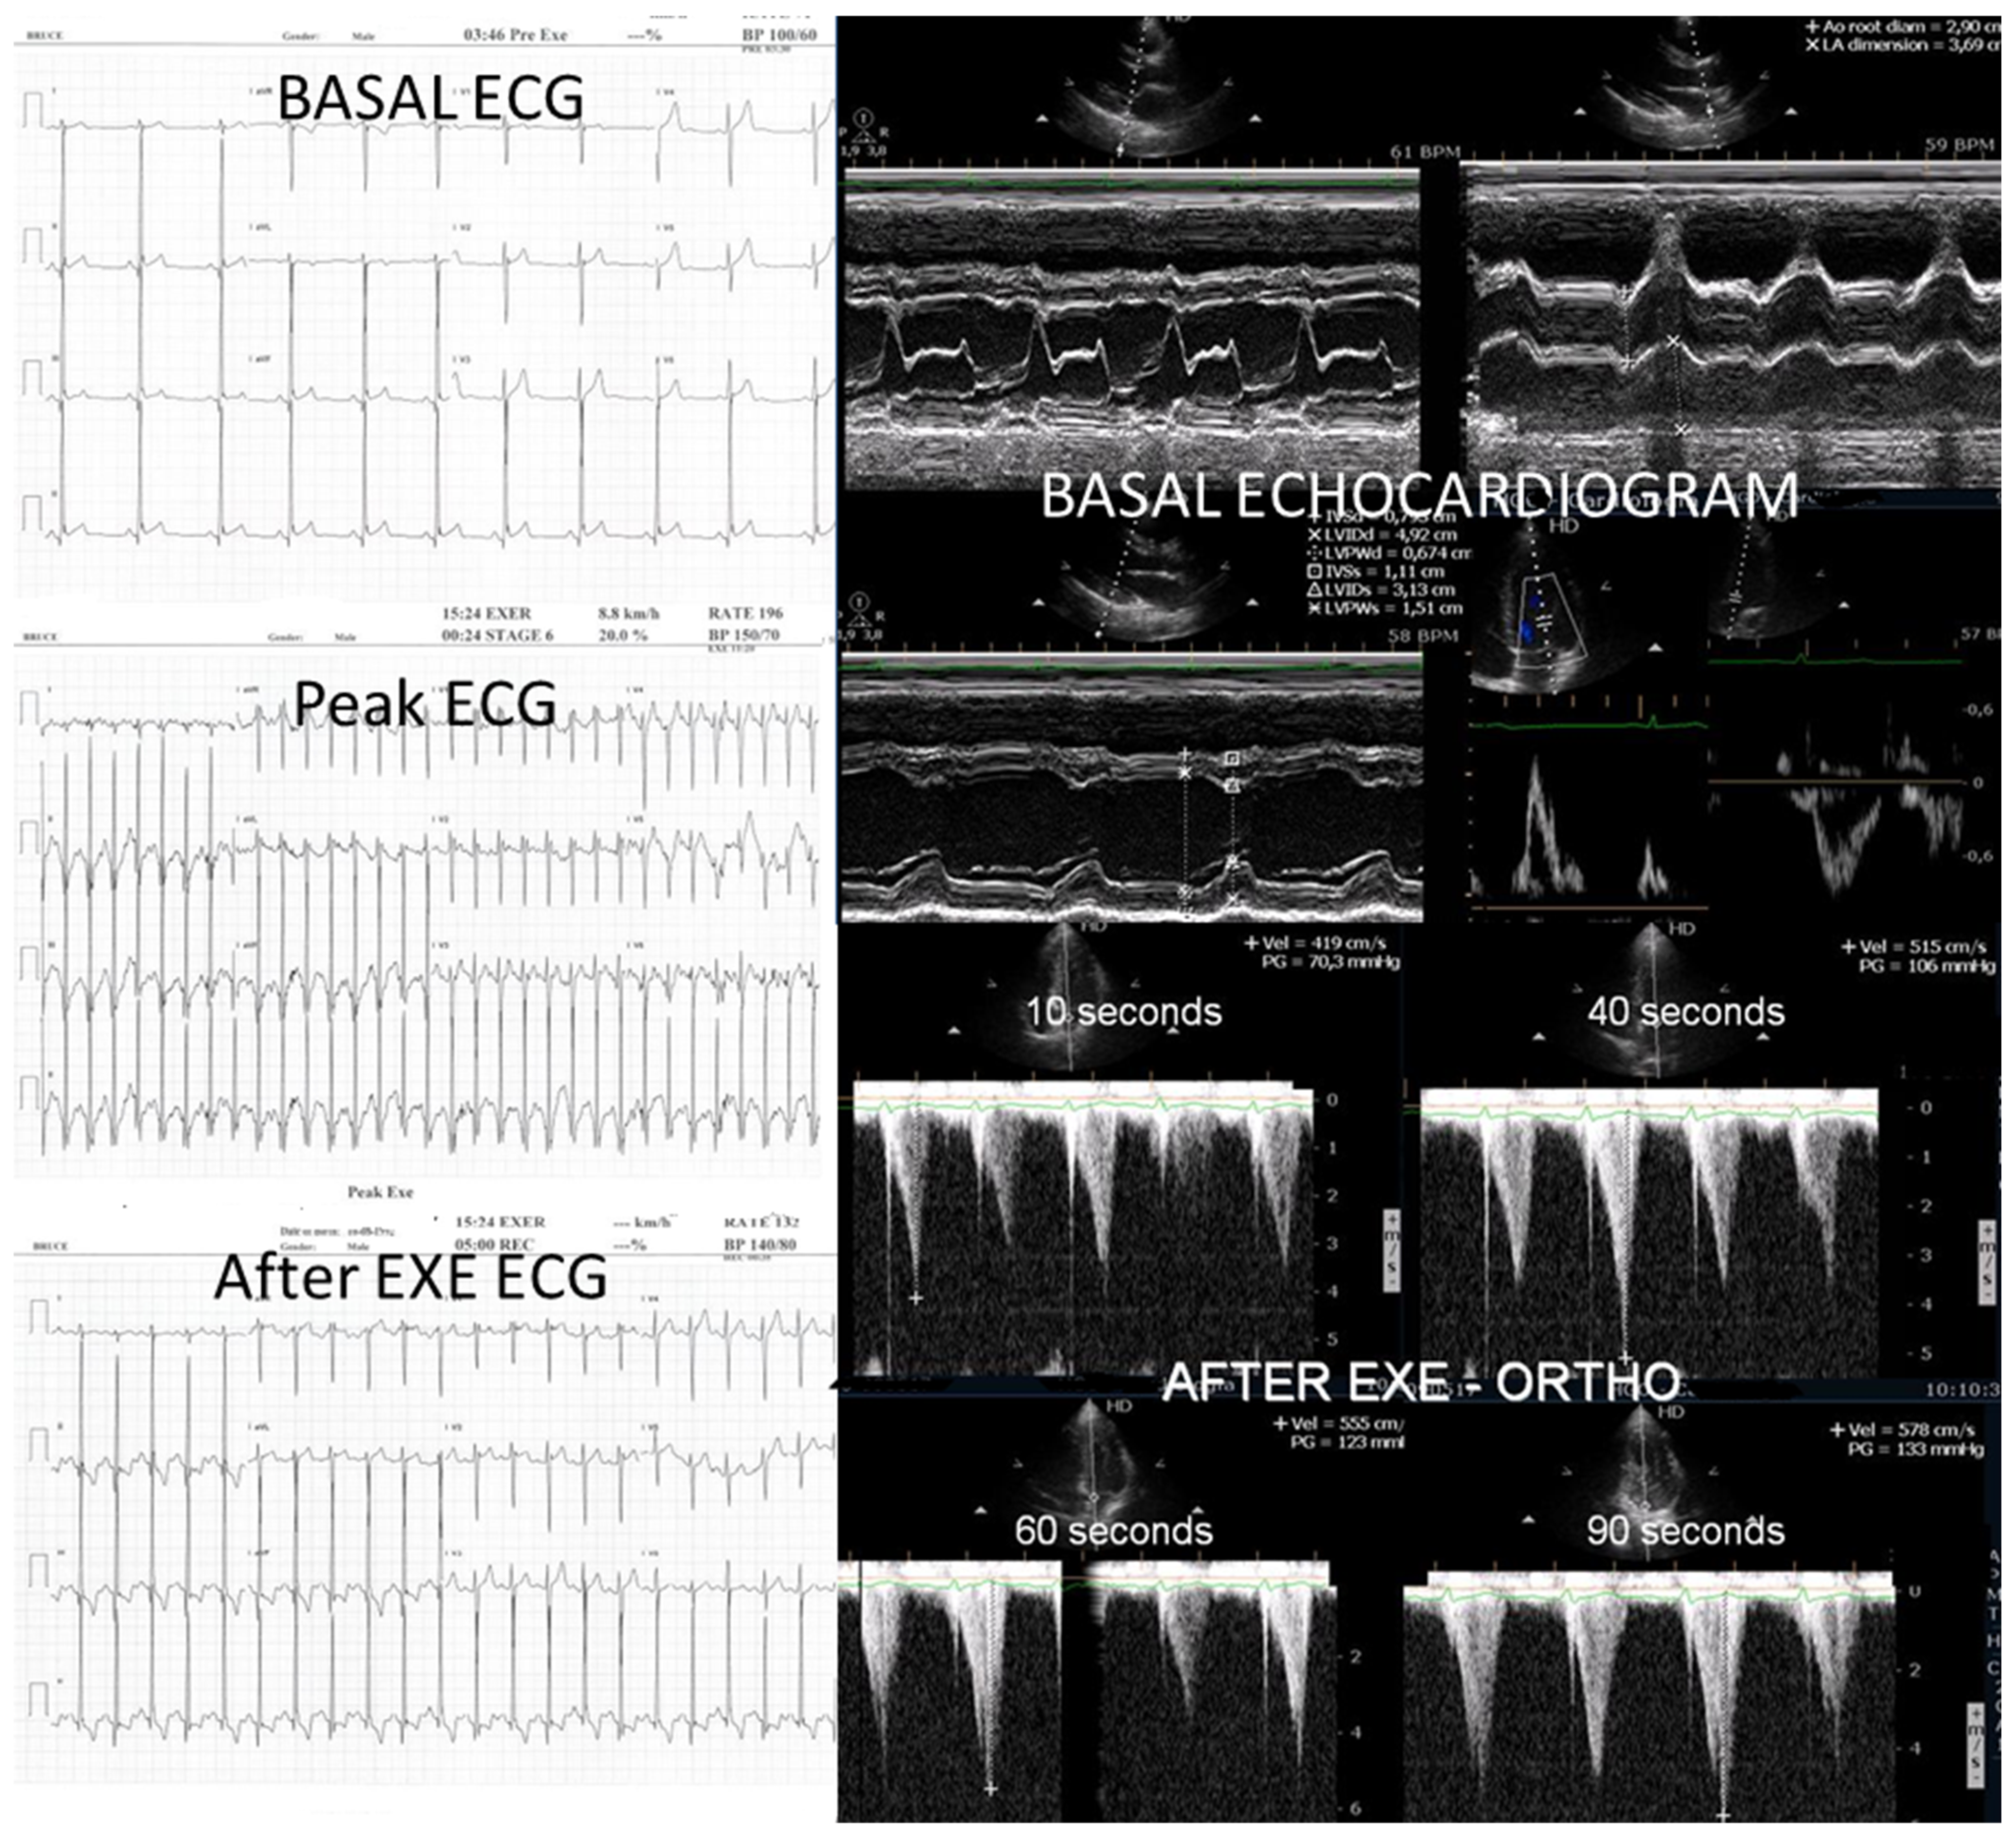

We observed the development of intraventricular pressure gradients (IVPGs) in adolescents without left ventricular hypertrophy upon assumption of an upright posture prior to exercise—a phenomenon previously described in patients with hypertrophic cardiomyopathy [3]. At the onset of exercise (Figure 5), the IVPG initially decreased, likely due to increased preload resulting from activation of the lower limb musculature. However, as exercise progressed, the IVPG steadily increased (Figure 6). After exercise, maintaining an upright posture led to a more pronounced reduction in preload, compared to a supine position. This hemodynamic shift likely accounts for the post-exercise elevation in IVPG observed in most adolescents studied. This postural response may also explain the orthostatic recovery IVPG observed in one highly symptomatic adolescent who presented with exertional angina and ST-segment abnormalities (Figure 7). Additionally, Figure 8 illustrates the impact of beta-blocker therapy on ESE findings in one patient, including the titration of atenolol to a dose of 50 mg, underscoring the clinical relevance of individualized treatment.

Figure 7.

This composite image from an adolescent in the study with post-exercise angina shows ST alterations suggestive of ischemia occurring simultaneously with IVPG.